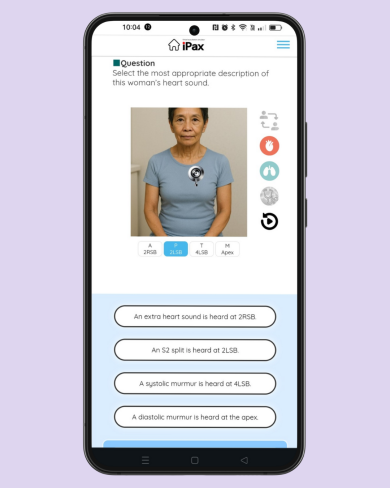

Daily quiz

2025/06/15

On June 15, a case study of an 81-year-old woman with a heart murmur was posted. Please check which auscultation site reveals which characteristic heart sounds. (June 15, 2025)

この記事を読む